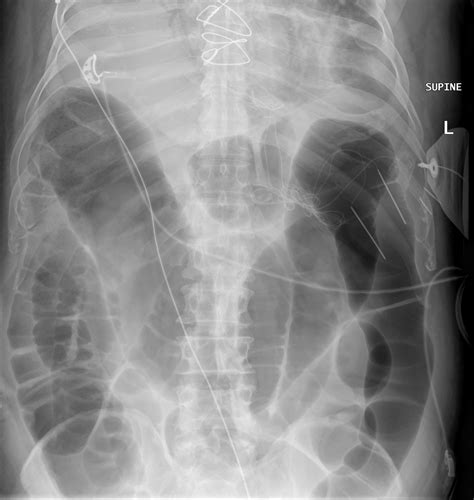

Diagnosis of an Incarcerated Inguinal Hernia

Diagnosing an incarcerated inguinal hernia typically involves a combination of a physical examination and imaging tests. The healthcare provider will:

• Examine the groin area for a visible bulge and tenderness.

• Ask about symptoms such as pain, nausea, and difficulty passing gas.

• Order imaging tests such as an ultrasound or CT scan to confirm the diagnosis and assess the extent of the incarceration.

Imaging tests are crucial for determining the severity of the incarceration and whether there is any sign of strangulation. An ultrasound can provide a clear view of the hernia and the surrounding tissues, while a CT scan can offer a more detailed image of the abdominal area.

• Bowel Obstruction: The trapped tissue can cause a bowel obstruction, preventing the passage of stool and leading to severe abdominal pain and distension.